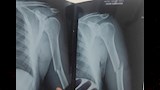

أعلنت مديرية الصحة بالمنيا، عن نجاح فريق طبي في إجراء عملية جراحية دقيقة وناجحة داخل مستشفى الصدر، لشاب يبلغ من العمر 22 عامًا، يعاني من مرض العظم الزجاجي (Osteogenesis Imperfecta)، وهي حالة وراثية نادرة تجعل العظام شديدة الهشاشة وعرضة للكسور المتكررة.

ووفقًا لبيان المديرية، فقد تعرّض الشاب لحادث أدى إلى كسر في العضد الأيمن، وعلى الفور جرى نقله إلى المستشفى، وتم تثبيت الكسر بنجاح باستخدام شرائح ومسامير.

ويُعاني المريض من تاريخ سابق من الكسور في عدة مواضع مختلفة بجسده بسبب طبيعة مرضه، ويتلقى أيضًا علاجًا منتظمًا لتنظيم ضربات القلب.